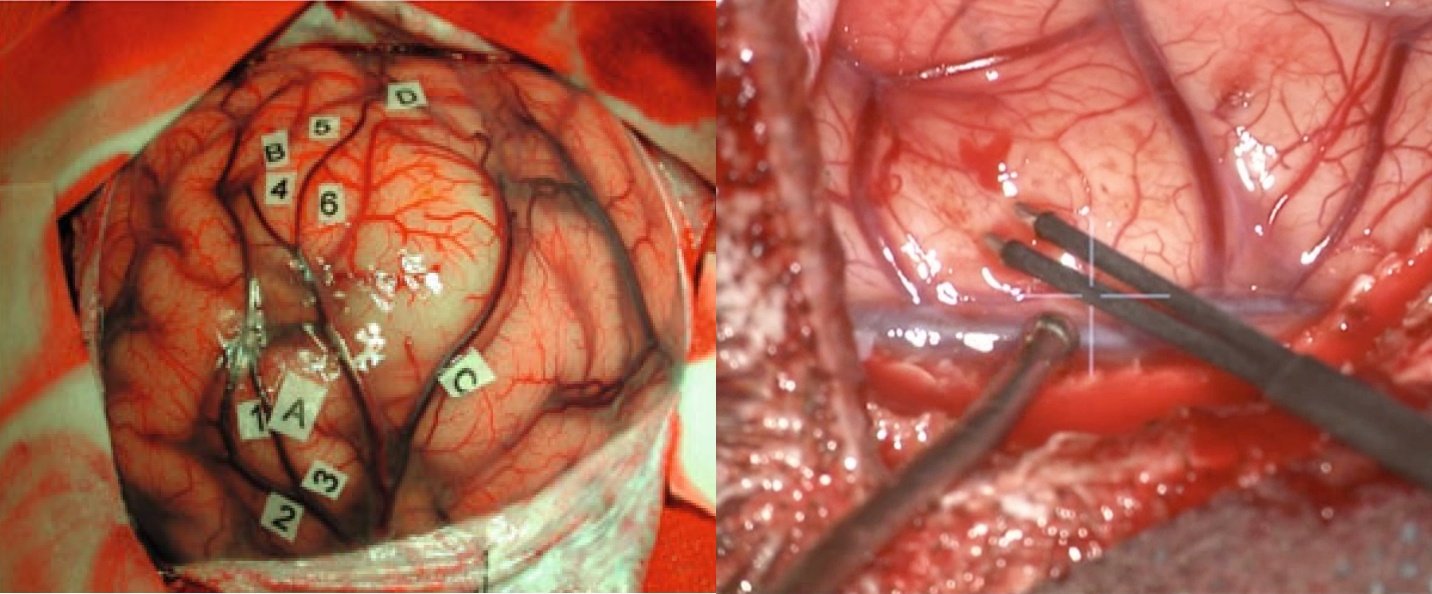

Chirurgia – rol central, dar nu curativ

Chirurgia reprezintă primul pas terapeutic și unul dintre cei mai importanți factori prognostici modificabili.

Conceptul actual este cel de rezecție maximală sigură, care implică:

- îndepărtarea cât mai extinsă a tumorii vizibile

- conservarea funcțiilor neurologice esențiale

Extensia rezecției este direct corelată cu supraviețuirea, însă beneficiul se pierde dacă este însoțit de deficit neurologic semnificativ.

Tehnologiile moderne au crescut semnificativ siguranța:

- fluorescența 5-ALA permite identificarea țesutului tumoral activ

- neuronavigația oferă orientare spațială precisă

- monitorizarea neurofiziologică protejează funcțiile motorii

- chirurgia awake permite cartografierea limbajului și a funcțiilor cognitive

În practică, fiecare intervenție este o negociere fină între radicalitate și funcție.